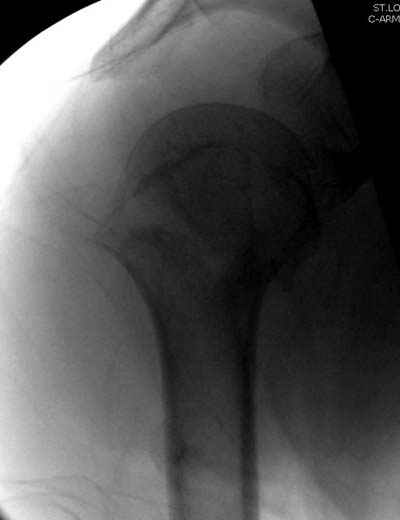

Сегодня взял больного повторно в операционную, не скажу, что повторная репозиция через неделю после первой попытки, была простая.

После удаления спиц попытался манипулировать отломками, но безуспешно, поэтому пришлось пользоваться периостальным элеватором, чтобы устранить смещение отломков и перепровести спицы. Проверил и перепроверил стабильность фиксации под ЭОПом, завтра Рг- будет готов, вот и поглядим....

Посылаю послеоперационные Рг граммы.

Всего Доброго,

Поздравляю, получилось просто замечательно. Если можно, расскажи чуть подробнее, как делали - как вправляли, как вводили спицы, поворачивали ли их?

Я и сам доволен результатом. В предпоследнем письме я кратко описал ход операции - закрыто репонировать не удалось( 2 недели с момента травмы и 1 неделя после неудачной репозиции) после удаления пучков спиц, пришлось сделать - 2см разрез на уровне перелома и с помощью периостального элеватора (золотое правило механики) *одеть* головку на дистальный отломок.

Спицы проводил через старые отверстия, вращая пучок импактором- направителем при его введении в головку.